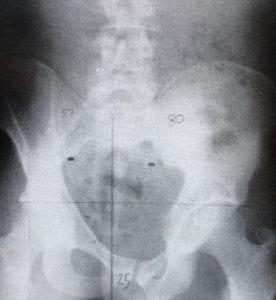

Illustration snedhet

Före och efter behandling (rtg-bilder hämtade från Plaugher/ Lopes Textbook of Clinical Chiropractic)

Asymmetri/ Symmetri